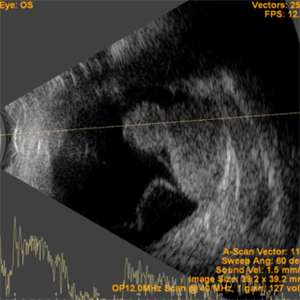

Collar Button Appearance on B-Scan

Aug 28 2019 by Gayathri Mohan

B-scan showing an intraocular mass with collar button appearance. Suspected case of choroidal melanoma.

Photographer: Dr.Gayathri Mohan, Retina Foundation

Imaging device: Nidek Mirante SLO

Condition/keywords: choroidal mass, collar button